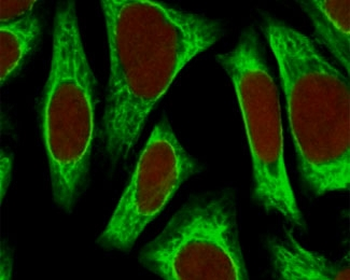

Immunofluorescent staining of fixed human HeLa cells with Smooth Muscle Actin antibody (clone SPM332, green) and NucSpot nuclear stain (red).